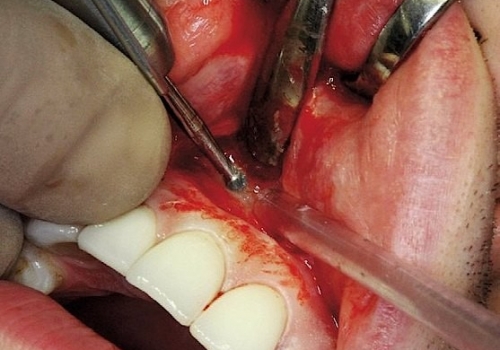

Bu zaman bəzi hallarda kanal müalicəsinin yenidən icrası (endodontik reviziya) mümkün olsa da, bir çox hallarda bu və ya digər səbəbdən həyata keçirilməsi mümkün olmur. Bu zaman əsas tətbiq edilən müalicə metodu dişi çəkməmək şərti ilə, iltihab ocağının uzaqlaşdırılmasını təmin edən – diş kökünün rezeksiyası metodudur. Bu əməliyyat vasitəsilə iltihab ocağı diş kökü ilə birlikdə kənarlaşdırılır və kök kanalları xüsusi metodla yenidən işlənir və doldurulur. Əməliyyat əsasən yerli ağrısızlaşdırma altında, xüsusi böyüdücü vasitənin tətbiqi ilə həyata keçirilir.